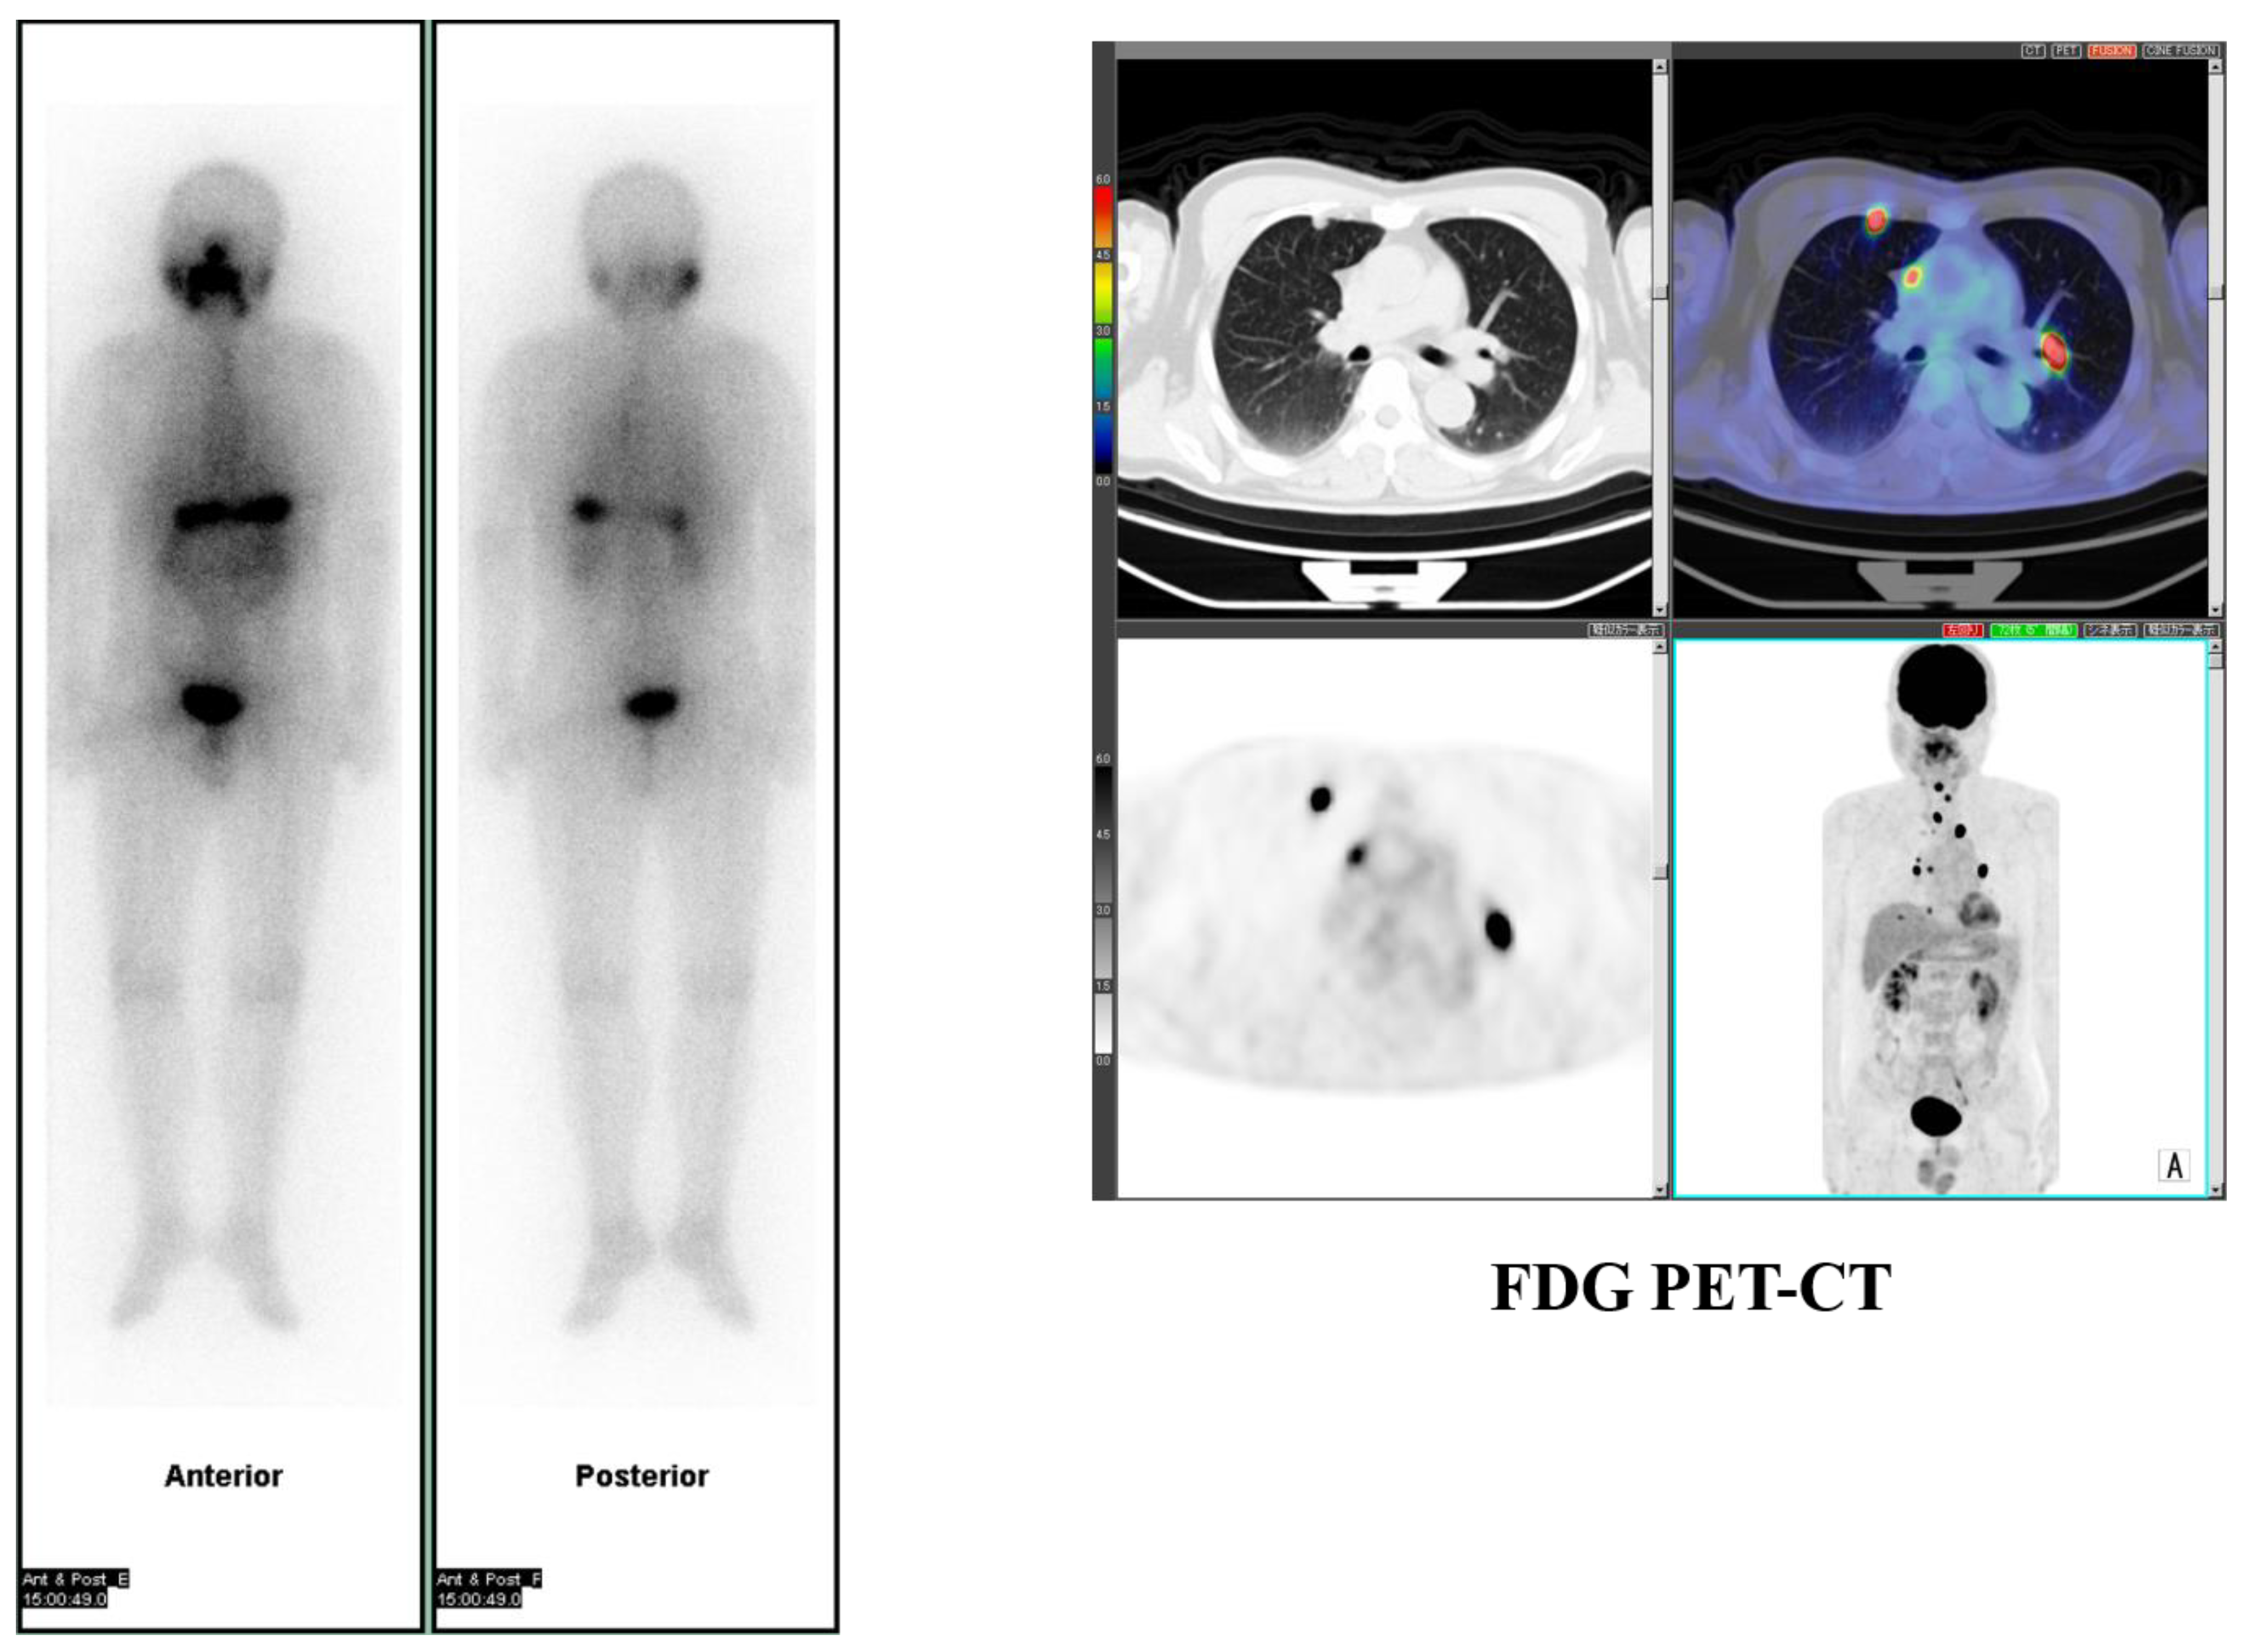

- Tokue, A.; Higuchi, T.; Oriuchi, N.; Arisaka, Y.; Endo, K. Clinical significance of 2-[18F]fluoro-2-deoxy-d-glucose positron emission tomography for the assessment of 131I-metaiodobenzylguanidine therapy in malignant phaeochromocytoma. Eur. J. Nucl. Med. Mol. Imaging 2011, 38, 1869–1875. [Google Scholar] [CrossRef]

- Yoshinaga, K.; Abe, T.; Okamoto, S.; Uchiyama, Y.; Manabe, O.; Ito, Y.M.; Tamura, N.; Ito, N.; Yoshioka, N.; Washino, K.; et al. Effects of Repeated 131I-meta-iodobenzylguanidine Radiotherapy on Tumor Size and Tumor Metabolic Activities in Patients with Metastatic Neuroendocrine Tumors. J. Nucl. Med. 2020. Online ahead of print. [Google Scholar] [CrossRef]